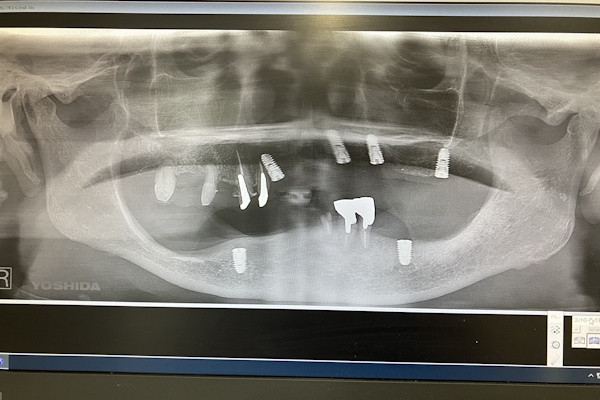

レントゲン画像